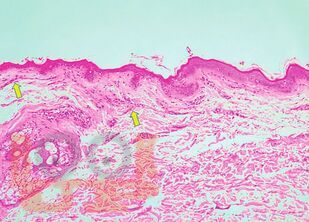

Судебно-медицинская экспертиза механической асфиксии и постасфиктической болезни

Судебно-медицинская экспертиза механической асфиксии и постасфиктической болезни : учебно-методическое пособие / М. А. Кислов, А. В. Максимов, О. В. Лысенко, Д. А. Карпов. - М. : Практическая медицина, 2025. - 140 c.. - (Библиотека судебно-медицинского эксперта). - ISBN 9785988118329. - Текст : электронный // ЭБС "Букап" : [сайт]. - URL : https://www.books-up.ru/ru/book/sudebno-medicinskaya-ekspertiza-mehanicheskoj-asfiksii-i-postasfikticheskoj-bolezni-19593927/ (дата обращения: 11.05.2026). - Режим доступа : по подписке.